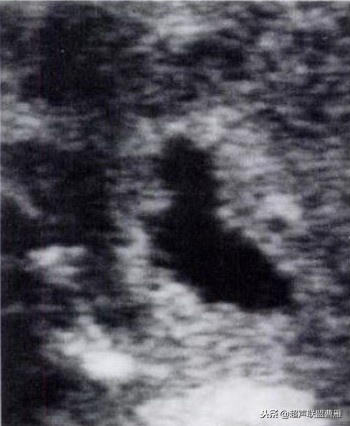

孕龄5.8周,胚极2.5mm,卵黄囊8mm,死胎

孕龄7+5周卵黄囊10.3mmx9.5mm,胚胎死亡

有的文献将卵黄囊内径的最大限度定为6.1mm

小卵黄囊,预后不良

钙化卵黄囊6.6mm,一周后胚胎死亡